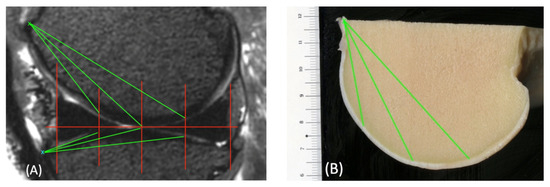

The base of the femur trochlea was used as a reference point from which the distance to the ROIs was measured in the MRI images (Figure 7). This was then used in the macroscopic images to find the corresponding ROI.

Figure 7. Sagittal view of the medial femorotibial joint in a 3D T2-weighted VIEW sequence (A) and the condyle in a macroscopic scan (B), with marked regions of interest (ROIs, red lines). The base of the condyle (green x) is marked. From this point, the distances to each ROI were measured (green lines). This distance could then be used to find the corresponding ROIs in the macroscopic scans. The same was carried out for the tibia using the tuberositas tibiae (blue x) as the reference point.